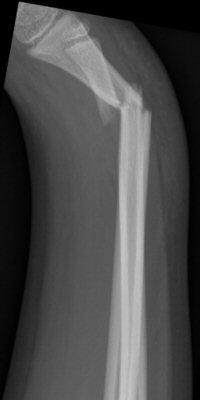

Distala diafysära radius- och ulnafrakturer, opererade med TEN-spikar, sista bilderna läkt efter 7 månader. Alla bilderna är från samma patient.